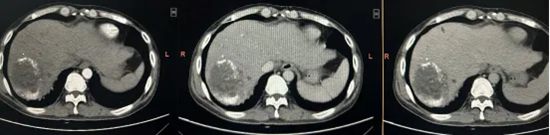

为给患者争取根治机会,陈艳军主任团队反复判读影像资料,详细评估病情,周密制定方案,最终决定实施腹腔镜右半肝切除术。

肿瘤体积巨大且紧邻下腔静脉,手术难度极大,稍有不慎将会出现难以控制的大出血,危及患者生命。

最终,手术历时约4小时,陈艳军主任团队冷静应对,精准解剖肝门Glisson系统,依次安全处理肝动脉、门静脉、肝静脉及肝短静脉,沿肝中静脉精准离断肝实质,在彻底切除肿瘤的同时,最大限度保留正常肝脏组织,实现了微创、精准、低出血、保功能的理想效果。